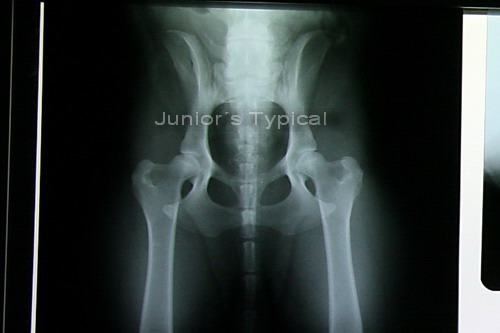

![]() |

| Eine sehr gute Lagerung ist wichtig. |

| Damit solche Aufnahmen gelingen. |